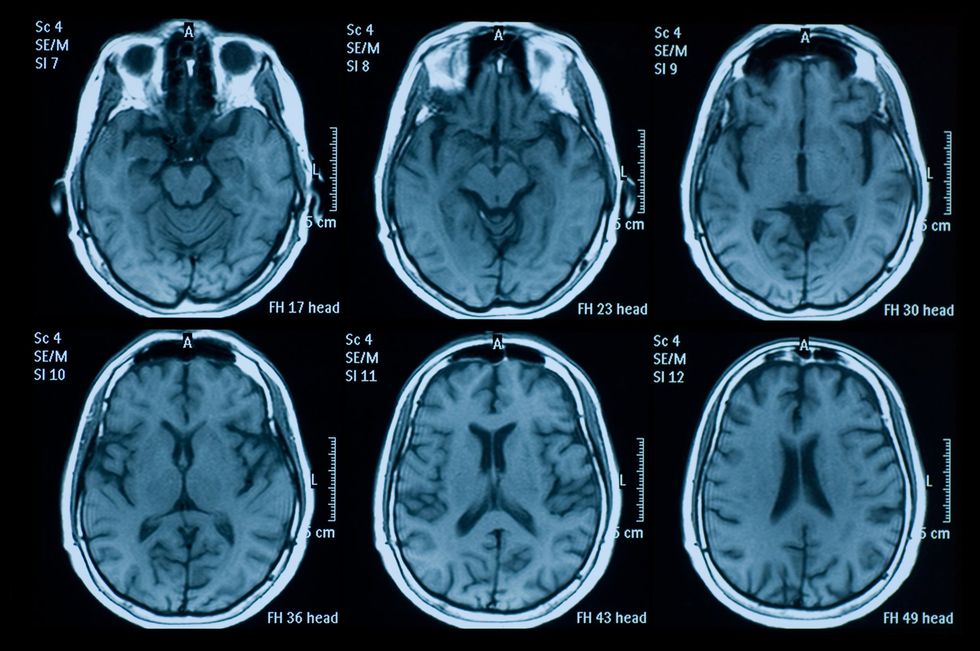

He added that medical schools never taught him brain cells could grow, but MRI scans now show compelling evidence in people who consistently make brain-healthy choices.